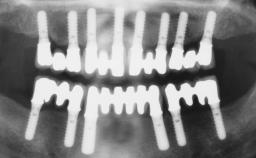

Doctor of dental surgery. Head of the Department for Implantology at the University of Geneva. Head of the Division for Stomatology, Oral Surgery and Dento-Maxillo-Facial Radiology of the Department for Dental Medicine at the University Geneva. Fellow of the ITI.